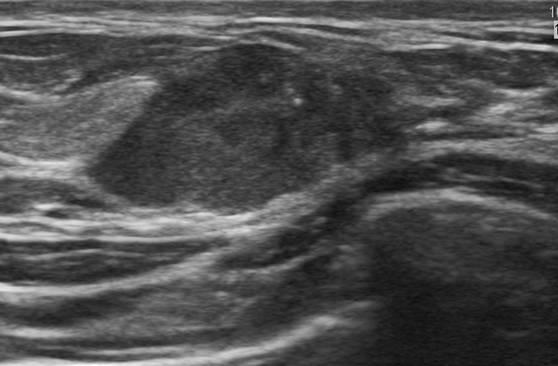

Ung thư vú

» Thông tin: Nữ giới – 33 tuổi.

» Lâm sàng: Khối tuyến vú.